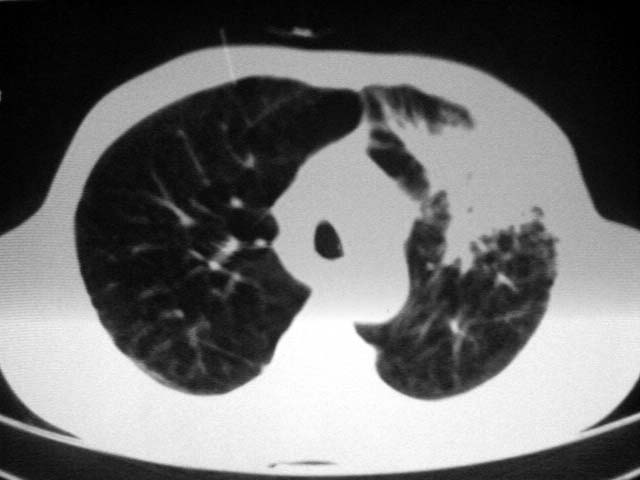

以下是引用zjzjr在2007-9-4 17:00:00的发言:[br]双上肺继发型结核伴左上肺空洞形成.慢性支气管炎伴肺气肿.

以下是引用liuzheng_9326在2007-9-4 16:23:00的发言:[br]痰检未见结核菌, 治疗后症状好转。图像符合陈旧性结核伴感染。